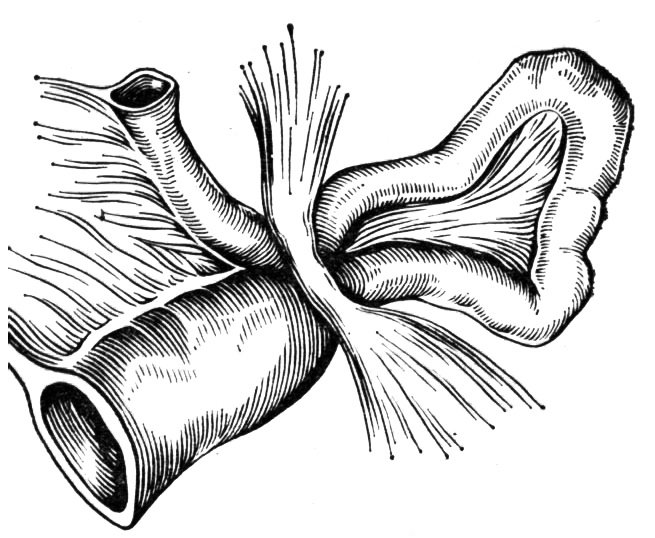

Иллюстрации и информация о симптомах острого кишечного непроходимости